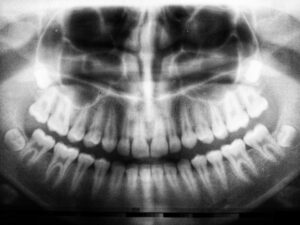

While we always aim to preserve your natural teeth whenever possible, there are times when removal is the best option for your oral health. Whether due to decay, advanced gum disease, or damage, we can perform most extractions right here in our office.